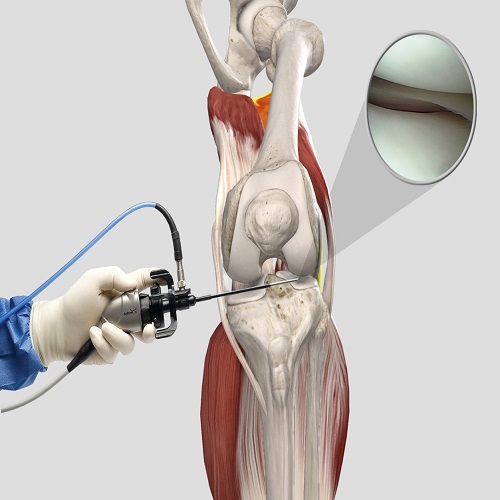

Artroskopik Menisküs Onarımı Nedir? Artroskopik menisküs onarımı, diz eklemindeki menisküs adı verilen kıkırdak dokusunun, minimal invaziv bir cerrahi prosedür olan artroskopi yöntemiyle onarılması işlemidir. Menisküs, diz eklemleri içinde bulunan C şekilli kıkırdak yapıdır ve ek yüzeylerin düzenli bir şekilde yük görünümünü sağlar. Ancak travma, aşırı zorlanma veya yaşlanmaya bağlı olarak menisküs yırtılabilir. Artroskopik menisküs onarımı,…